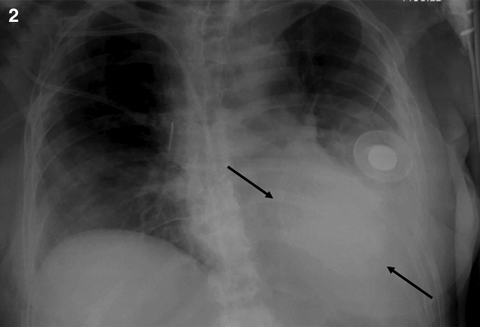

On the GHPS (Figure 1) a radiolucent pericardial halo was apparent, raising concerns for pericardial effusion. The rest of the study was unremarkable, with normal regional wall motion and quantitative ejection fraction of the cardiac ventricles. Comparison with a recent chest x-ray (Figure 2) revealed radiolucency external to the chest wall. Subsequent transthoracic echocardiography (Figure 3) ruled out the presence of pericardial effusion.

2: Anteriorposterior chest x-ray showing the saline-filled breast implant as a radio-opaque shadow on the left anterior chest wall (arrows). |